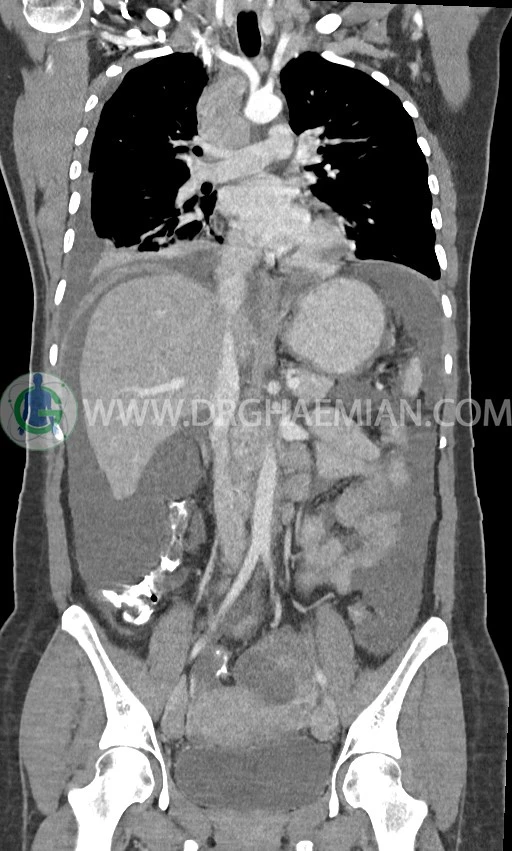

سی تی اسکن ریه با استفاده از اشعه ایکس تصاویر عرضی مقطعی از ریه و بالا تنه ایجاد می کند. در این کیس افیوژن پلور، لنفادنوپاتی، تخریب ریه سمت راست، توده پستان، آسیت و توده تخمدان دیده می شود.

در سی تی اسکن اسپیرال ریه، مدیاستن و شکم و لگن با کنتراست خوراکی و وریدی (مولتی دیدکتور 16 با مقاطع ظریف و بازسازی های ساژیتال و کرونال) :

لنفادنوپاتی فراون با حداکثر SAD=25mm در مدیاستن

لنفادنوپاتی با حداکثر SAD = 12mm در سوپراکلاویکل چپ (level 4) و در level 6 و level 7

pleural effusion قابل توجه دوطرفه همراه با passive collapse سگمان های بازال (با شدت بیشتر در سمت راست)

توده با حدود صاف و واضح به قطر 17mm درمدیال پستان راست و با حدود لوبوله به قطر 20mm در قسمت خارجی- فوقانی پستان راست